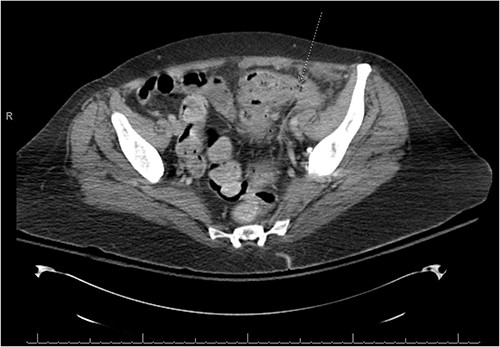

There was a suspicion of underlying abdominal infection causing her altered mental status given the presence of abdominal pain and low grade fever. A computed tomography (CT) scan of the chest, abdomen and pelvis was completed to assess for prior or current malignancy. Acute on chronic sigmoid diverticulitis with a left colo-ovarian fistula and a 4.3 cm left adnexal abscess was found (Figs 1 and 2); yet, no evidence of malignancy was noted. Antibiotic therapy was initiated, and interventional radiology was consulted for abscess drainage. Cancer antigen (CA)-125 and carcinoembryonic antigen (CEA) were only mildly elevated and attributed to generalized inflammation.

A fistulous connection from the sigmoid colon to the ovary is suggested. A dotted line arrow points out the connection.

There is a thick-walled enhancing, 3.9 × 4.3 × 4.2 cm3 perisigmoidal collection containing nondependent gas and fluid with adjacent inflammatory fat stranding, suggestive of tubo-ovarian abscess.